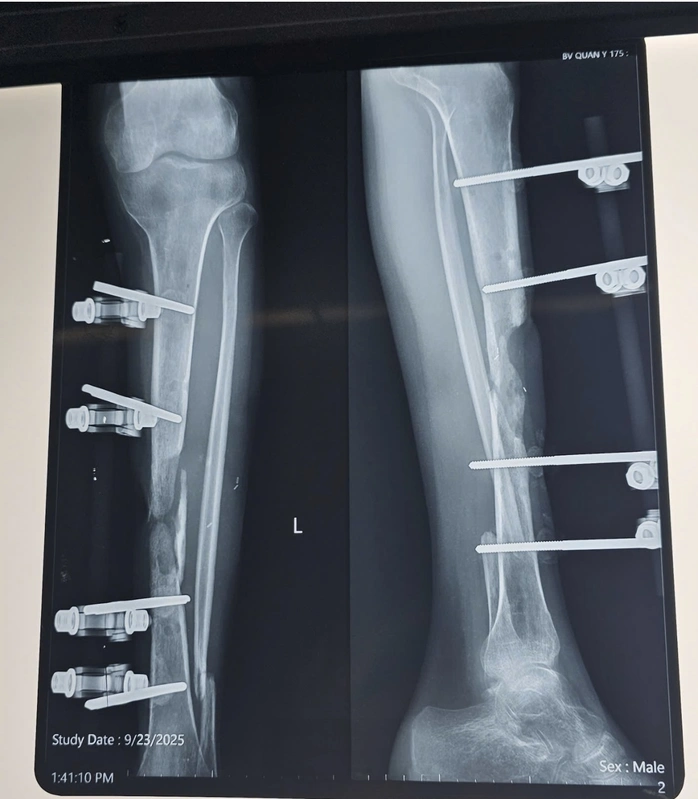

Nam bệnh nhân V.T.L (20 tuổi) bị gãy hở 2 xương cẳng chân trái đã được phẫu thuật đặt khung cố định ngoài, sau đó diễn biến viêm xương tủy xương điều trị nhiều đợt đến khi ổn định.

Ngày 23-9, anh L. nhập viện vào Khoa Bỏng và Vi phẫu tạo hình-Viện Chấn thương Chỉnh hình (Bệnh viện Quân y 175) trong tình trạng bị sẹo mổ cũ vùng trước xương chày xơ dính, còn khung cố định ngoài, khuyết xương chày khoảng 8 cm, gãy cũ xương mác trái, chân trái ngắn hơn chân phải khoảng 2 cm, không còn biểu hiện viêm hay nhiễm trùng.

Bệnh nhân được phẫu thuật cắt bỏ đoạn xương viêm, làm mới ổ gãy; chuyển phức hợp vạt da xương mác tự do từ chân đối diện nối vào bó mạch chày trước cẳng chân trái bằng kỹ thuật vi phẫu, kết hợp xương bằng nẹp vít.

Sau 14 ngày phẫu thuật, vạt da hồng hào, siêu âm tại vùng nhận vạt mạch máu lưu thông tốt, đảm bảo vạt sống 100%, hình ảnh X-quang cho thấy xương thẳng trục, chiều dài 2 chân bằng nhau. Bệnh nhân hồi phục tốt, sinh hoạt bình thường, không có biến chứng sau mổ.